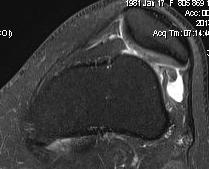

1. Isolated Patella tilt

Indications

- clinical and xray patella tilt

- no instability / malalignment

- excessive lateral pressure syndrome

5. Trochlea dysplasia

- trochleoplasty

4. Lateral Trochlea Elevation

- still unstable after above operations

- small lateral incision

- beware fracturing lateral femoral condyle

- need to be able to take bone graft from iliac crest